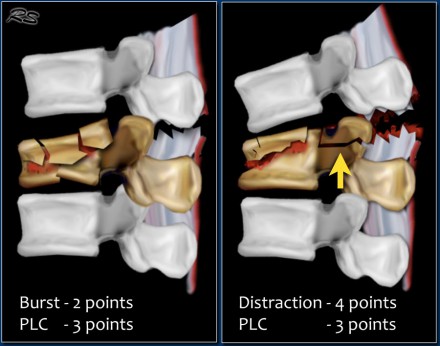

When there are several fractures, each level has to be scored separately.

The level with the highest TLICS score will determine the type of treatment.

For example, in a translation/rotation injury, the PLC is always involved, making a total of 3+3=6 points.

When there is a distraction on the posterior side, the PLC is always involved, making a total of 4+3=7 points.

In case of a distraction on the anterior side, however, the PLC may or may not be involved, i.e. it will be either 4 or 4+3= 7 points.

In some cases it can be difficult to decide whether there is a burst fracture with a torn PLC or distraction with a torn PLC and a compression fracture (figure).

You have to decide what you think is the main issue: the collapse of the vertebral body or the distraction.

Since in both cases the TLICS score based on imaging will be high, there is usually an indication for surgical treatment.

In some cases it is difficult to decide whether you are dealing with distraction combined with a compression fracture or with a compression fracture with PLC-injury.

If the distraction is the main feature, then the morphology is distraction, i.e. 4 points.

In these cases the PLC is always involved, resulting in a total of 7 points for the TLICS-score.

If compression is the main feature, then the morphology is burst, i.e. 2

points combined with the PLC injury making a total of 5 points.

In both cases the patient is a surgical candidate.